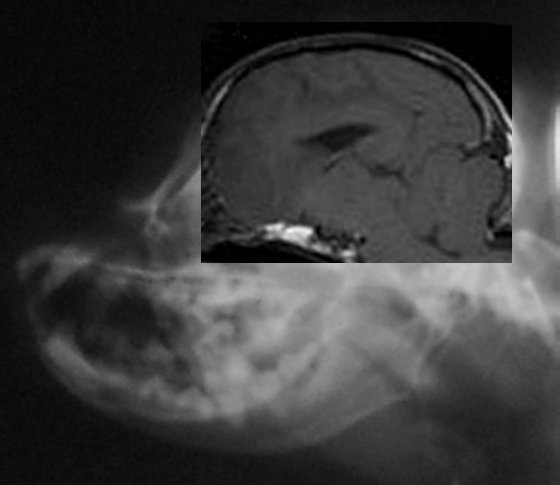

Below are more side skull x-rays of dogs who have also been MRId.

Their diagnosis will be listed below the comps. The idea is to

see if any differences in skull shape could be ascertained from

a simple skull x-ray. Next to it the MRI was fit into the skull

x-ray, just to see where everything fits in. Below is the

result. So far there appears to be a considerable difference in

the shape of the back of the skull between the dogs with SM and

without!

Dog above has moderate to severe malformation and SM with

symptoms